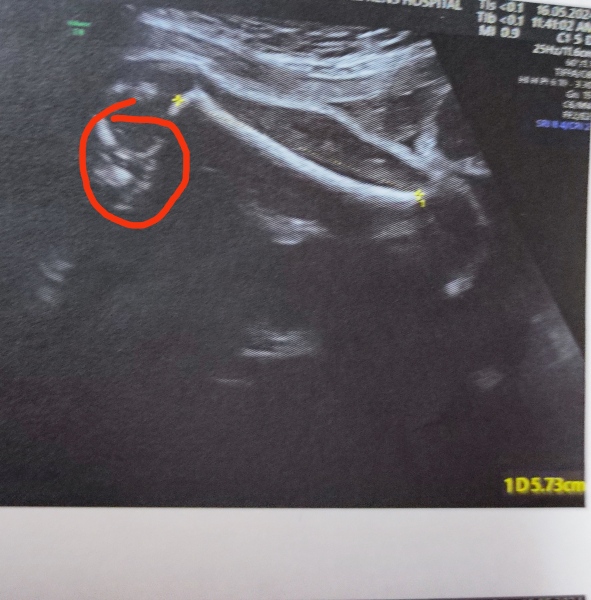

Hello everyone. I would like to know the gender of my baby . Am attaching the femur shot measuring length 5.73CM in my 30 th week scan. I was not able to recognize the gender during my scan. My husband don't want to find out the gender actually. But am curious to know. Any suggestions please?

Thanks for commenting. May I know where the genitalia located? Left or right side of the image? Highlighted the part but is it correct?